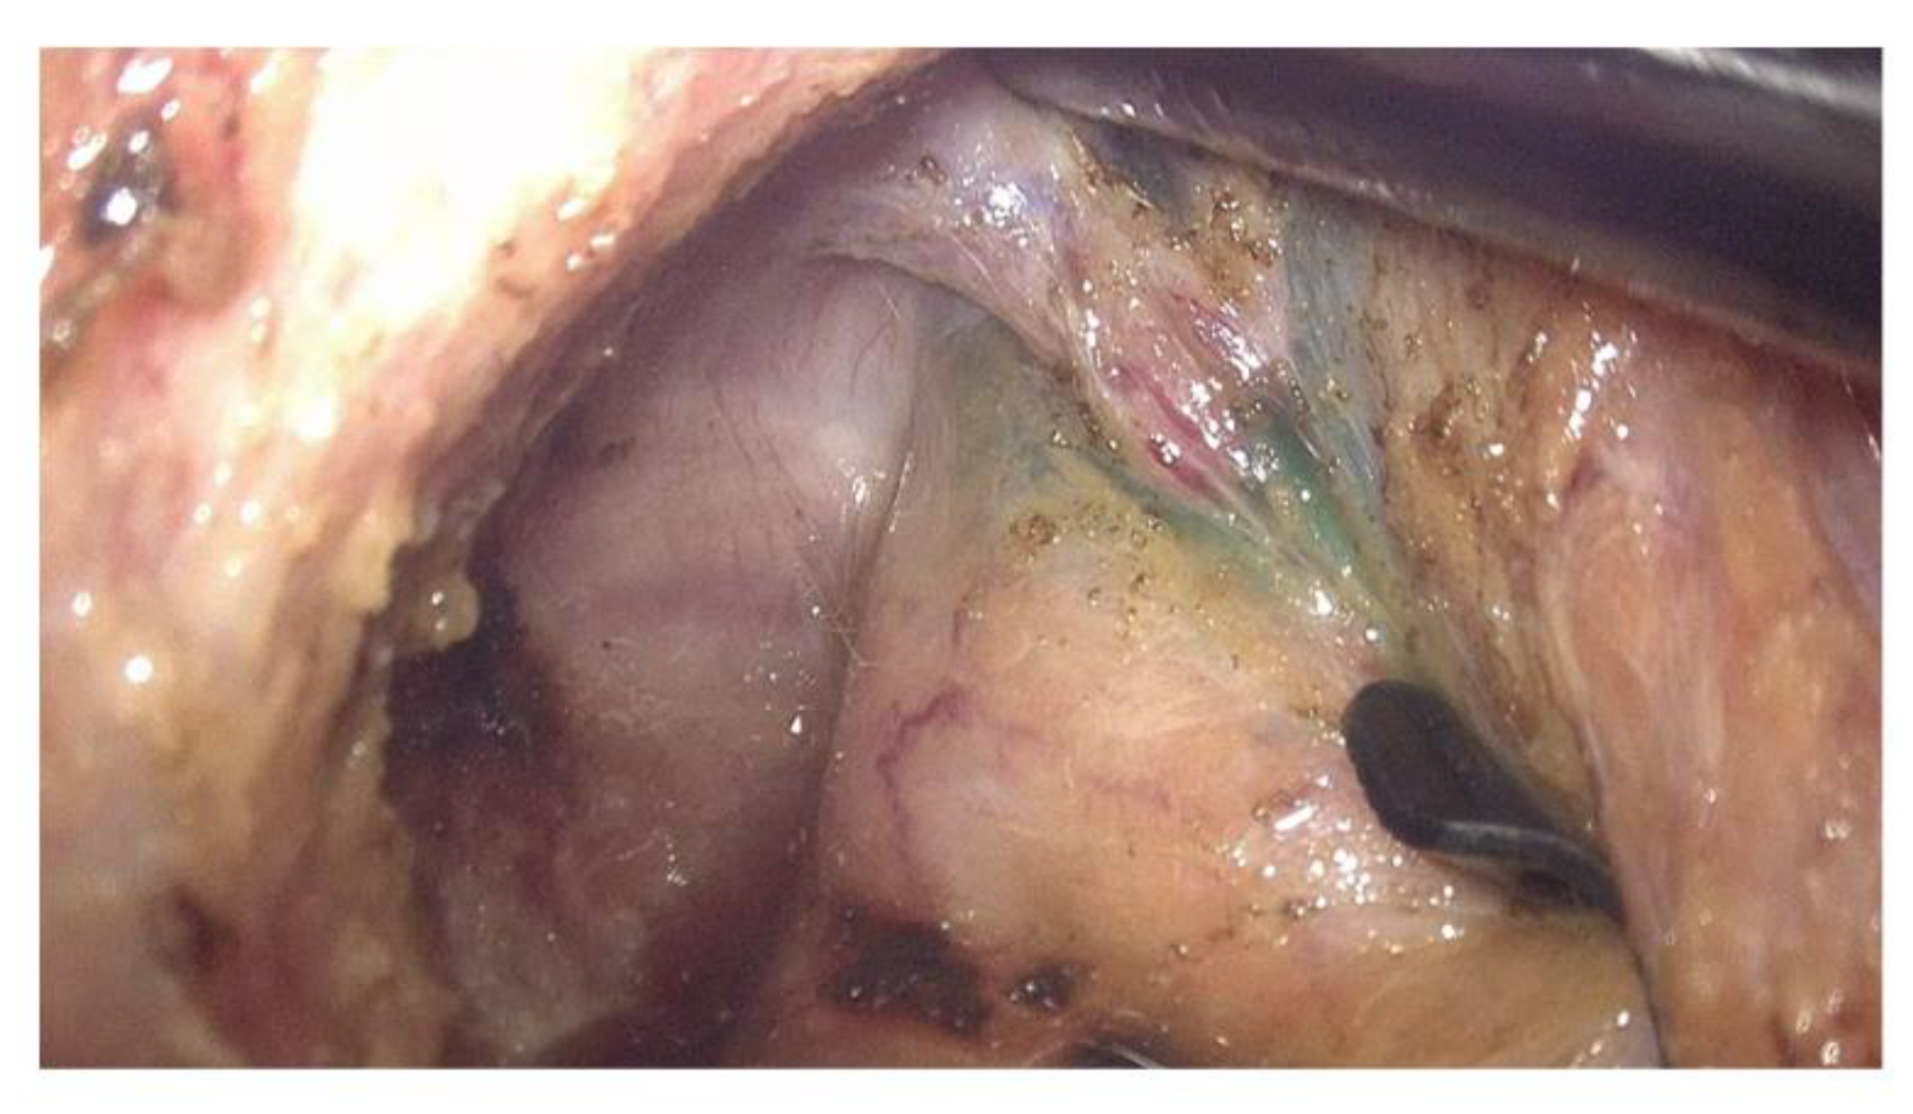

2.2. Intraoperative ICG Fluorescence Imaging

| 4 | M | 50 | 2 | Yes | Long-course | Lap ISR | 3 | 1a | 0 | + | + | + |